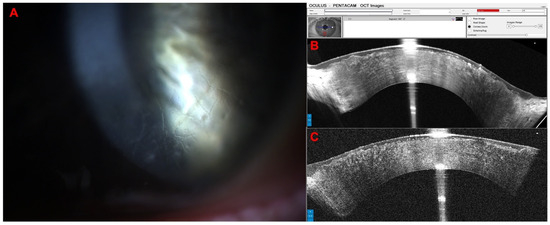

Combined Rotating Ultra-High-Resolution Spectral Domain OCT and Scheimpflug Imaging for In Vivo Corneal Optical Biopsy

1.3. The Pentacam® Cornea OCT